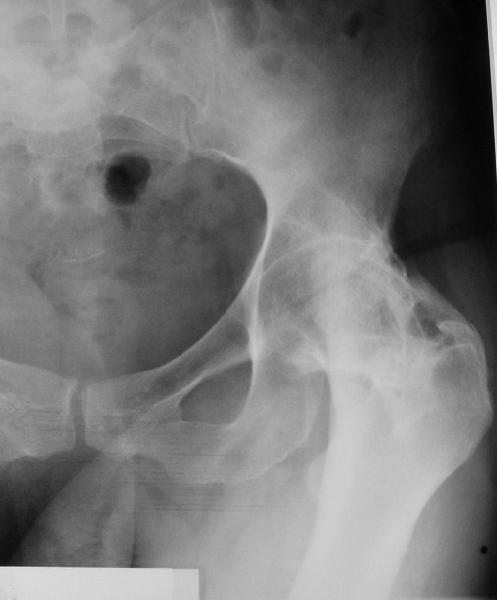

У больной 53 лет в последний год появились сильные боли в пояснице.

3 года назад при нефрэктомии по поводу гидронефроза была перфорация кишки, перитонит, сепсис, колостома. Месяца 2 в реанимации. Все это завершилось благополучно, колостома вскоре была закрыта.

При обследовании выявлен анкилоз тазобедренного сустава в приведении. Видимо, в период пребывания в тяжелом состоянии появились гетеротопические оссификаты. За исключением того, что осталась одна почка, сейчас других медицинских проблем нет.

Пациентку в первую очередь беспокоят боли в спине, на отсутствие движений в суставе она вроде и не жалуется. Вопрос насчет тактики. Корсет и анальгетики вряд ли решение. Первый вариант - удаление оссификатов и эндпротезирование, второй - корригирующая остеотомия в проксимальном отделе с устранением порочного положения.

Второй вариант много проще и менее травматичен. Можно ли без размыкания сустава рассчитывать на существенное уменьшение боли за счет устранения перекоса таза?